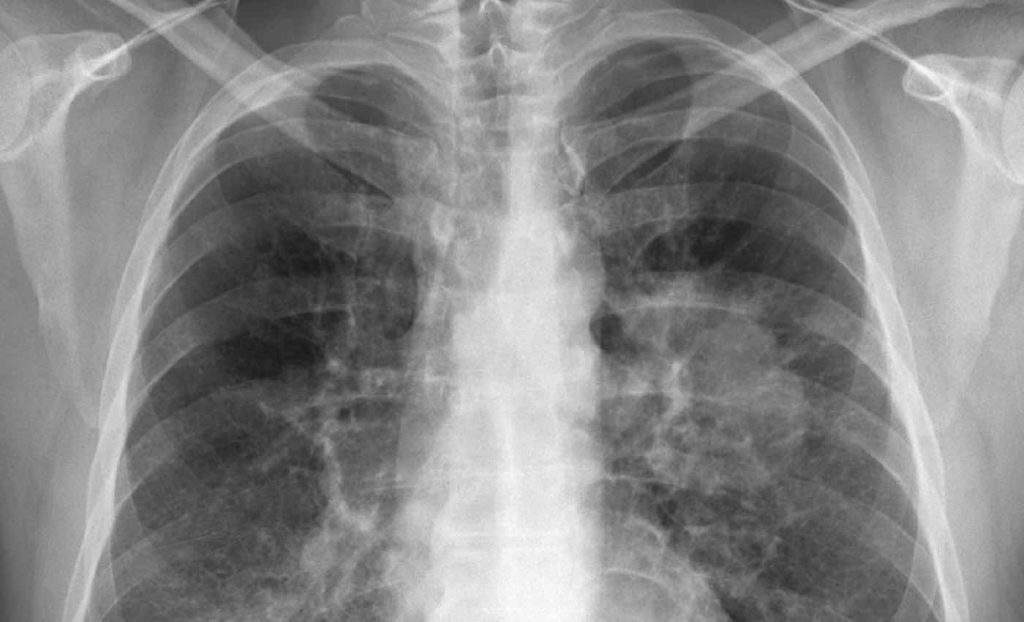

Radiografía de un cáncer de pulmón

Investigadores del Consejo Superior de Investigaciones Científicas (CSIC), organismo dependiente del Ministerio de Ciencia, Innovación y Universidades, han demostrado la eficacia de un nuevo medicamento en un contexto de adenocarcinoma pulmonar resistente a un tratamiento previo.